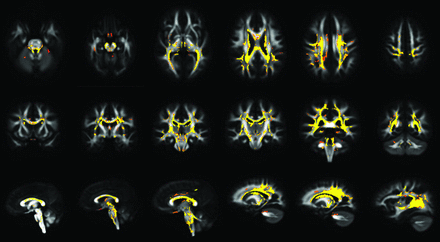

Voxel-based DTI results for the whole-brain voxel-based analysis demonstrated significant differences (P < .001) of FA values between patients with CP and HCs: Visual group comparison detected a diffuse reduction of FA values in both the supratentorial and infratentorial WM (Fig 1). The areas affected were bilaterally located in the superior and inferior cerebellar peduncles (including decussation), motor and sensory tracts in the brain stem, posterior limbs of internal capsules, peritrigonal WM (including the optic and thalamic radiations), external capsules, centrum semiovale, corpus callosum (with a prevalent involvement of its central portion), fornix, cingulum, chiasm, and optic tracts. The same regions in the supratentorial WM showed increased MD, AD, and RD values at the same significance level (P < .001) (On-line Fig 2). No significant differences were detected for MD, AD, and RD in the brain stem and cerebellum, except for an RD increase at the level of cerebellar and cerebral peduncles (On-line Fig 2). No regions in the brain showed increased FA or decreased MD, AD, and RD in patients with CP compared with controls.

Axial (first row), coronal (second row), and sagittal (third row) MR images show voxelwise FA group differences between patients with CP and HCs (FA patients < FA controls). Results are overlaid on the FA template obtained from all subjects, at a significance level of P < .001, corrected for multiple comparisons.